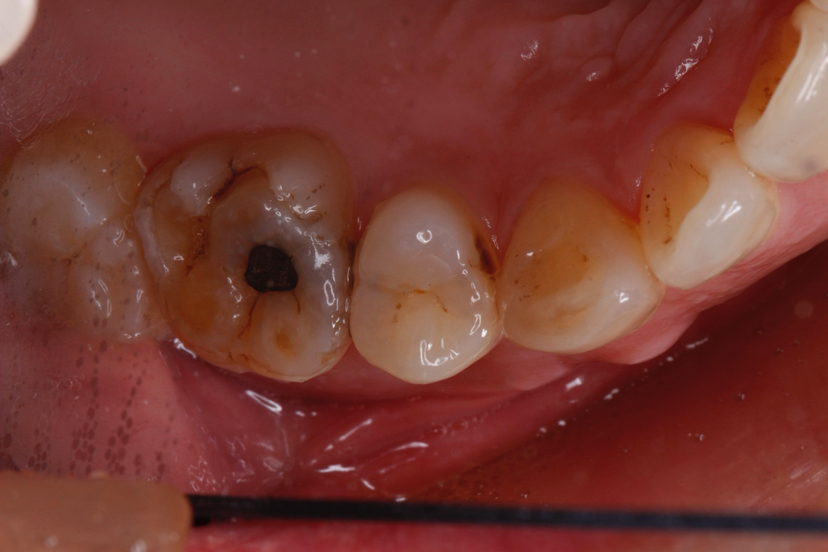

嵌体通常适用于以下情况:

✅ 后牙(磨牙)中度至重度缺损,传统补牙无法提供足够支撑时。

1. 检查与评估:医生检查牙齿缺损情况,判断是否适合嵌体修复。

2. 牙齿预备:去除龋坏部分,制备合适的嵌体窝洞。